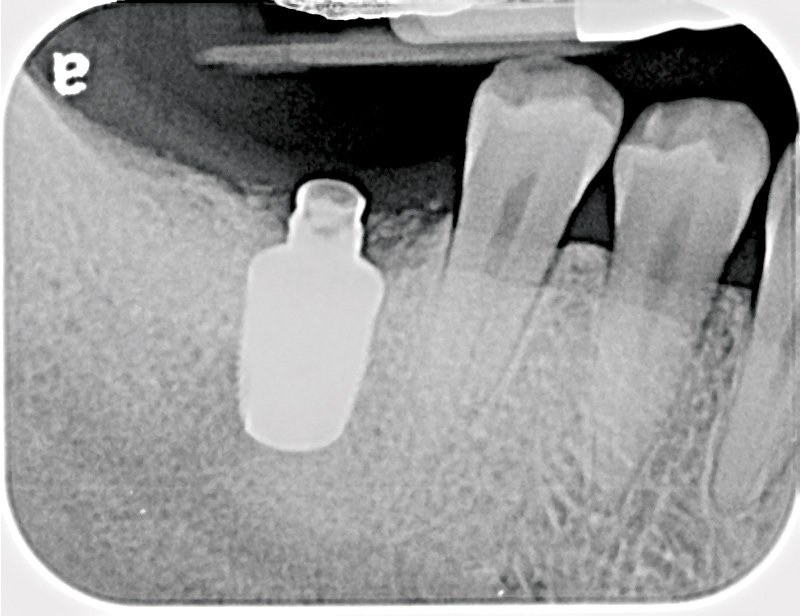

Fig 6. Radiograph following crown fracture.

Figure 6

Fig 13. Radiograph depicting peri-implantitis.

Figure 13